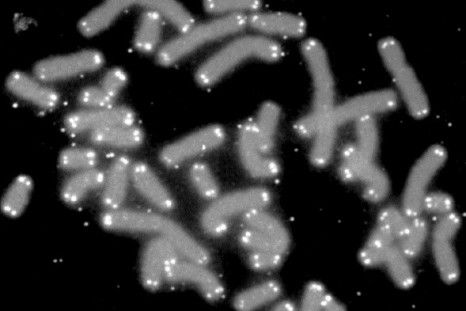

Genetic Mutation Increases Risk of Childhood Leukaemia

Scientists in 'uncharted territory' after finding genetic link to childhood leukaemia for first time.